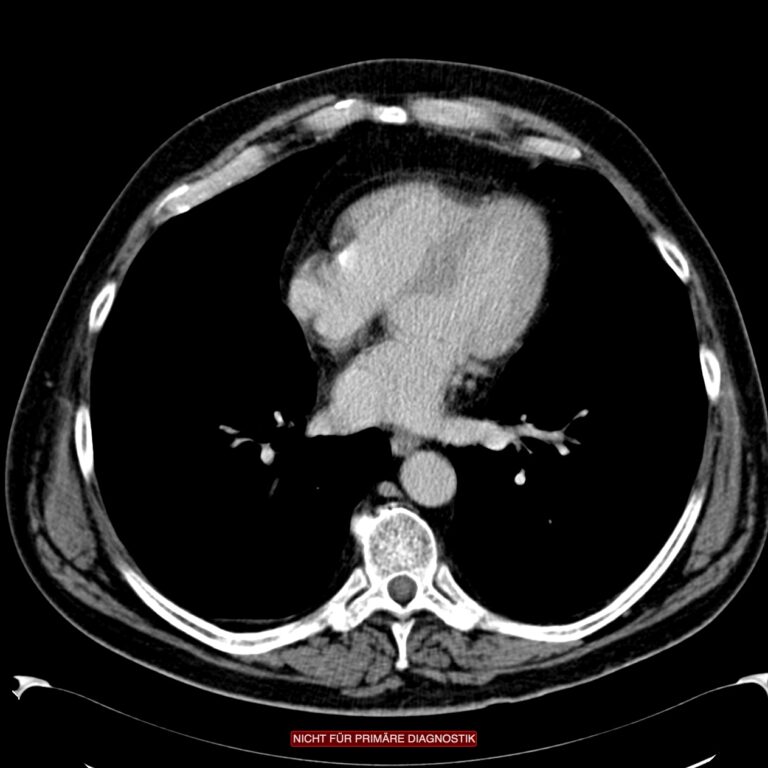

Die weitere Diagnostik, die zuverlässig hilft, den Schwergrad der Erkrankung einzuschätzen, ist die Computertomografie des Abdomens mit rektaler Kontrasmittelfüllung. Früher wurde oft ein Kolon-Kontrasmitteleinlauf zur Diagnostik eingesetzt. Mit dieser für diese Fragestellung heute obsoleten Untersuchungsmethode ließen sich zwar sehr schön die Divertikel darstellen, nicht aber das Geschehen außerhalb des Darmes. Da die akute Divertikulitis in ihrer Schwere aber durch die extraluminale Entzündungsreaktionen bestimmt wird, also durch die Peridivertikulitis, ist der Kolon-KE als diagnostisches Mittel hier unwirksam, weil der extraluminäre Teil der Entzündung nicht abgebildet werden kann.